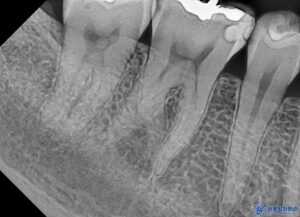

먼저 충치를 제거하였습니다.

충치가 비교적 깊은 위치까지

진행되어 있었으며,

그 영향으로 치아 뿌리 끝까지

염증이 퍼진 상태로 확인되었습니다.

이렇게 신경치료를

진행하였습니다.

본원은 MTA 신경치료를 진행하고 있는데,

우리 치과 신경치료의 경우,

보이지 않는 곳일지라도

좀 더 좋은 재료를 사용하여

하나를 치료해도 제대로 하고자

노력하고 있습니다.

특히 일반적으로 신경치료할 때

고무성분으로 충전하여 마무리를 하곤 하는데

신흥동치과 서울박사는 MTA라는

바이오세라믹 성분을 사용하여

신경치료를 하고 있습니다.